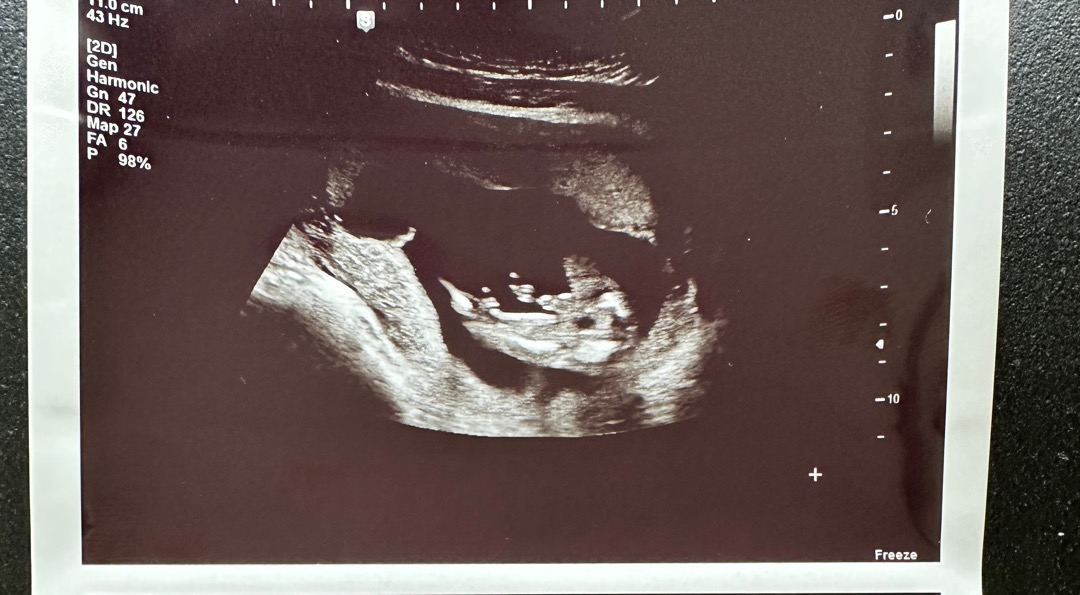

아들이네용

16주여서 오늘 병원다녀왔어요 ㅋㅋ 분명 12주차때는 아무것도 없더니 생겼네요

딸일거같다고했었어여